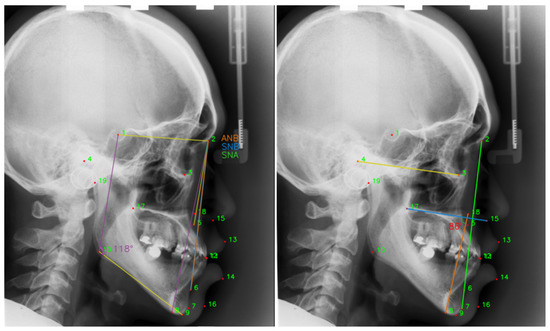

| Number | L1 | L2 | L3 | L4 | L5 | L6 | L7 | L8 | L9 | L10 |

| Anatomical Name | Sella | Nasion | Orbitale | Porion | Subspinale | Supramentale | Pogonion | Menton | Gnathion | Gonion |

| Number | L11 | L12 | L13 | L14 | L15 | L16 | L17 | L18 | L19 | |

| Anatomical Name | Lower incisal incision | Upper incisal incision | Upper lip | Lower lip | Subnasale | Soft tissue pogonion | Posterior nasal spine | Anterior nasal spine | Articulate |